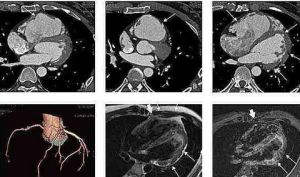

5.磁共振顯像(MRI)

對發現心室肌內局限性脂肪增多有較大價值。如套用可精確測定右心室容量的電影磁共振成像技術,可顯示右心室容量增大。